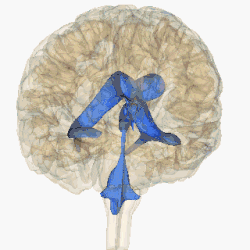

Każda z obu półkul mózgu zawiera w sobie jedną komorę boczną posiadającą łukowaty kształt, przypominający przechyloną nieco w dół literę „C”. W komorach bocznych wyróżnia się rogi przednie (cornu anterius ventriculi lateralis) sięgające do płatów czołowych, rogi dolne (cornu inferius) w płatach skroniowych, rogi tylne (cornu posterius) w płatach potylicznych oraz części środkowe. Komory boczne poprzez otwory międzykomorowe (foramina intraventricularia) łączą się z leżącą nieco niżej, ale położoną centralnie komorą III, znajdującą się częściowo w obrębie międzymózgowia. W tylnej części komory III rozpoczyna się wąski kanał – wodociąg mózgu, który nie zawiera splotu naczyniówkowego i przebiegając przez śródmózgowie łączy się z leżącą jeszcze niżej, również w linii środkowej, komorą IV. Ostatnia z komór znajduje się pomiędzy tylną częścią pnia mózgu a móżdżkiem. Komora IV posiada dwa otwory boczne (aperturae laterales ventriculi quarti) oraz jeden nieparzysty otwór pośrodkowy (apertura mediana ventriculi quarti), przez które płyn mózgowo-rdzeniowy przechodzi do przestrzeni podpajęczynówkowej.

Komory mózgu wypełnione są płynem mózgowo-rdzeniowym, który obmywa i amortyzuje mózg oraz rdzeń kręgowy wewnątrz struktur kostnych. Płyn jest produkowany przez wyspecjalizowane komórki wyściółki w splocie naczyniówkowym, który znajduje się we wszystkich elementach układu komorowego prócz wodociągu oraz tylnych rogów i przednich rogów komór bocznych. Płyn mózgowo-rdzeniowy przepływa z komór bocznych, poprzez otwory Monro, do komory trzeciej, a następnie przez wodociąg Sylwiusza do komory czwartej położonej w pniu mózgu. Z komory czwartej płyn mózgowo-rdzeniowy może przepłynąć do kanału środkowego rdzenia kręgowego lub do przestrzeni podpajęczynówkowej poprzez trzy nieduże otwory: pośrodkowy (Magendiego) i dwa boczne (Luschki).

Rycina przedstawiająca układ komorowy. Widok z boku.